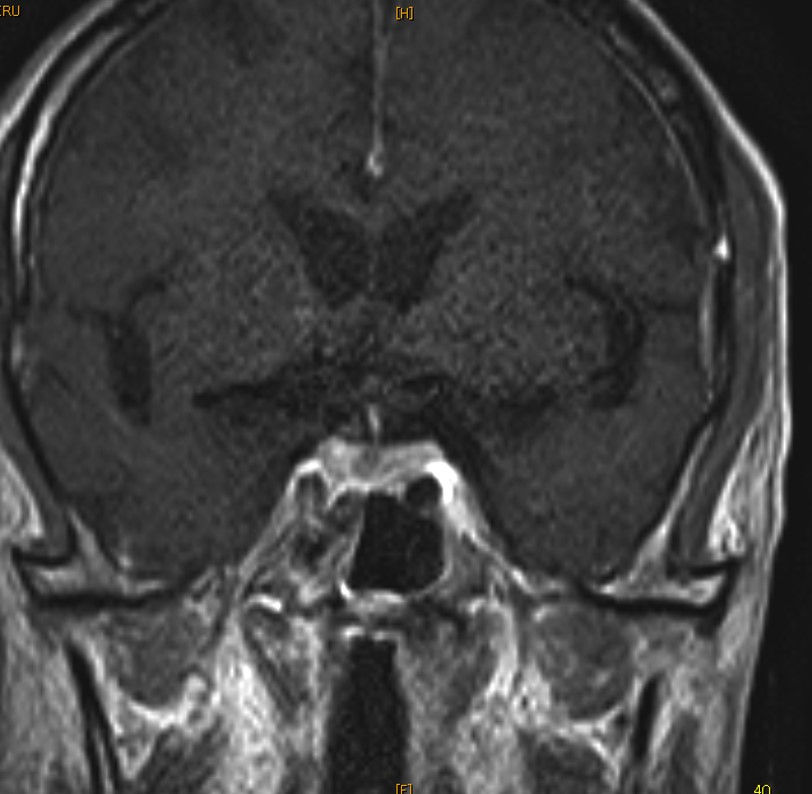

Initial differential diagnoses included hypopituitarism or non-thyroidal illness. Additional testing suggested hypopituitarism with somatomedin C 30 ng/ml, LH <0.10 mIU/ml and FSH 0.26 mIU/ml. The serum ACTH and cortisol were within normal limits. There is no response of TSH by TRH stimulation test. Contrast-enhanced brain MRI showed a mass-like lesion with the filling defect in the pituitary gland (Figure 1). Oral levothyroxine was initiated. Because of the high LDH level and splenomegaly, a possibility of malignant lymphoma was considered but a whole-body contrast-enhanced CT showed no lymphadenopathy. On the seventh day of hospitalization, he developed hypotensive and pancytopenia and died despite attempts of cardiopulmonary resuscitation.